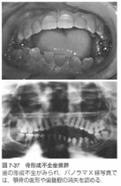

I型の一部(IB型),、W型の一部(WB型) に 歯の外套象牙質不全がみられます。

この場合,歯冠はオパール様の黄褐色半透明の色調を呈し、エナメル質が剥離しやすい.

歯髄腔の狭窄や消失,短い歯根,歯頚部の狭窄.

上顎骨劣成長や下顎過成長による反対咬合などがあります。